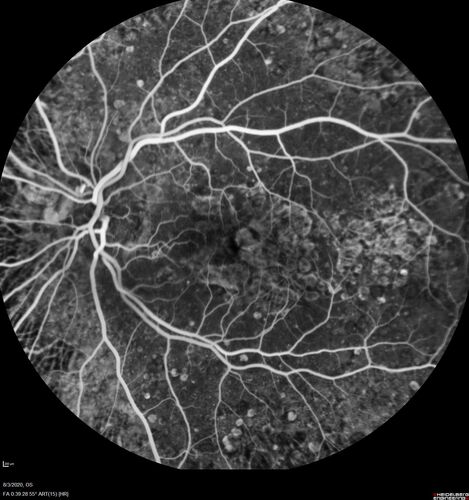

Age-related macular degeneration - Geographic Atrophy - Intermittent CME left eye from CRVO, Anemia, Diabetes

79 year old female - 3 years post CRVO in the left eye (20/32 VA) with intermittent CME.  Left eye is the better eye.  Vision is stable since 2 years ago

PMHx: Type II DM x 20 years, Chronic Anemia, Hyperlipidemia

VA 20/200 OD, 20/50 OS (usually 20/40)